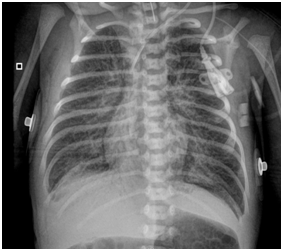

Newborn female was born at 37 weeks 5 days as a product of a second pregnancy, with prenatal diagnosis of duodenal atresia and esophageal stenosis (Figure 1). Due to a previous cesarean section and rupture of the membranes, an emergency caesarean section was performed. Birth weight was 2100 grams APGAR scores were 8–9 at…min. A thoracic-abdominal radiograph was performed, showing thorax without alterations and an image suggestive of duodenal atresia (Figure 2). An echocardiogram CIA 0.5, PCA: 0.2X0.3 showed mild dysplasia of aortic and pulmonary valves. Abdominal laparotomy at 24hours of life, revealed duodenal stenosis secondary to annular pancreas, intestinal malrotation and non-meconium plastic peritonitis without evidence of perforation. The defect was corrected by adhesiolysis, duodeno-duodenal anastomosis and incidental appendectomy.

Figure 1 Prenatal ultrasound: A) image of the double bubble suggestive of atresia/duodenal stenosis (stomach to the left and more centered the duodenum). B) Behind the heart, hyopecogenic image that corresponds to the dilated esophaguss.